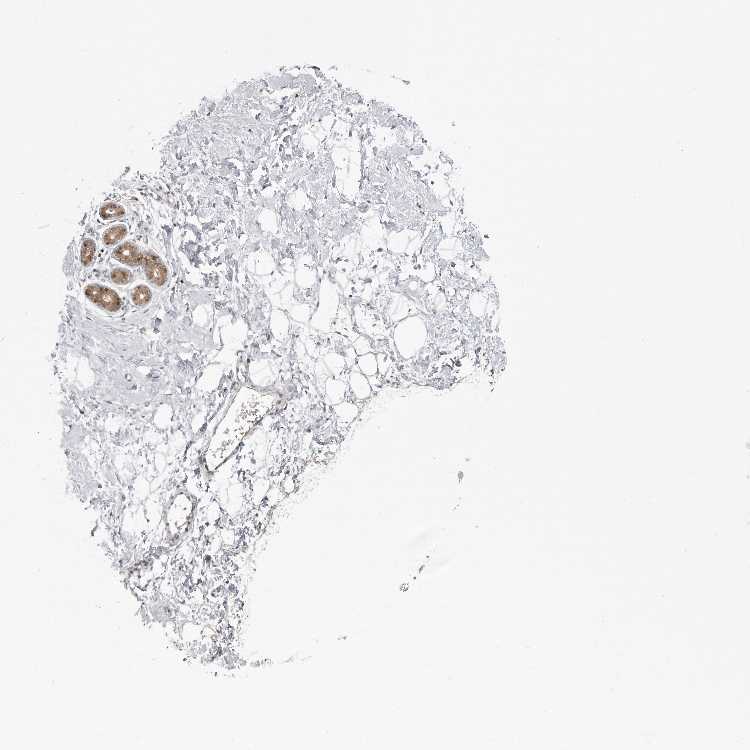

BREAST - Antibody stainingi

Antibody staining in the annotated cell types in the current human tissue is reported as not detected, low, medium, or high, based on conventional immunohistochemistry profiling in selected tissues. This score is based on the combination of the staining intensity and fraction of stained cells.

Each image is clickable and will lead to virtual microscopy that enables deeper exploration of all samples and also displays staining intensity scores, fraction scores and subcellular localization as well as patient and tissue information for each sample.

Antibody HPA007667Antibody CAB025854

Adipocytes Not detectedNot detected

Glandular cells LowMedium

Myoepithelial cells Not detectedMedium